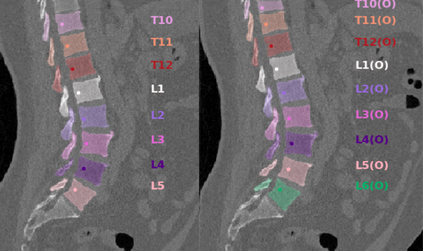

Vertebrae localization, segmentation and identification in CT images is key to numerous clinical applications. While deep learning strategies have brought to this field significant improvements over recent years, transitional and pathological vertebrae are still plaguing most existing approaches as a consequence of their poor representation in training datasets. Alternatively, proposed non-learning based methods take benefit of prior knowledge to handle such particular cases. In this work we propose to combine both strategies. To this purpose we introduce an iterative cycle in which individual vertebrae are recursively localized, segmented and identified using deep-networks, while anatomic consistency is enforced using statistical priors. In this strategy, the transitional vertebrae identification is handled by encoding their configurations in a graphical model that aggregates local deep-network predictions into an anatomically consistent final result. Our approach achieves state-of-the-art results on the VerSe20 challenge benchmark, and outperforms all methods on transitional vertebrae as well as the generalization to the VerSe19 challenge benchmark. Furthermore, our method can detect and report inconsistent spine regions that do not satisfy the anatomic consistency priors. Our code and model are openly available for research purposes.